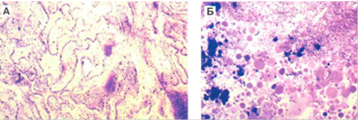

Дистрофические изменения сосудистого сплетения при хроническом перивентрикулярном энцефалите: А) отек ворсин, дистрофия эпителия; окраска гематоксилин-эозином, увеличение х 100; Б) бесструктурные белковые и известковые отложения в стромс сосочков; окраска по Массону, увеличение х 100.

В гистологической картине преобладает гиперплазия эпендимарных клеток и субэпендимарных фибриллярных астроцитов, инфильтрация лимфоцитами, макрофагами, плазматическими клетками стенок субэпендимарных сосудов.

Важнейшим компонентом в гистологической картине перивентрикулярного энцефалита являются изменения сосудистых стенок. К интраадвентициальным воспалительным инфильтратам подострой стадии, в позднем периоде присоединяются интенсивно выраженные пролиферативные изменения всех клеточных и волокнистых элементов стенок желудочков. При этом отмечается субэпендимарный глиально-волокнистый глиоз, гипертрофия астроцитов, разрастание аргирофильных волокон. Утолщение и гиалиноз стенок артерий и вен почти постоянно наблюдаются в микроскопической картине продуктивного перивентрикулярного энцефалита любого происхождения.

Эпендима местами слущена, местами пролиферирует с явлениями гипертрофии; погруженные в толшу субэпендимарного слоя, эпендимациты образуют "гнезда". В случаях "гранулярного эпендима-тита" на внутренней поверхности боковых желудоч-

ков обнаруживаются скопления эпендимы в виде бляшек, выросты смешанного глио-мезодермального состава. Часто поверхность стенок желудочков равномерно волокнистая и мелкобугристая. Различной длины дивертикулы просвета желудочков отделяют друг от друга возвышения, обычно выстланные непрерывной каймой эпендимарных клеток .